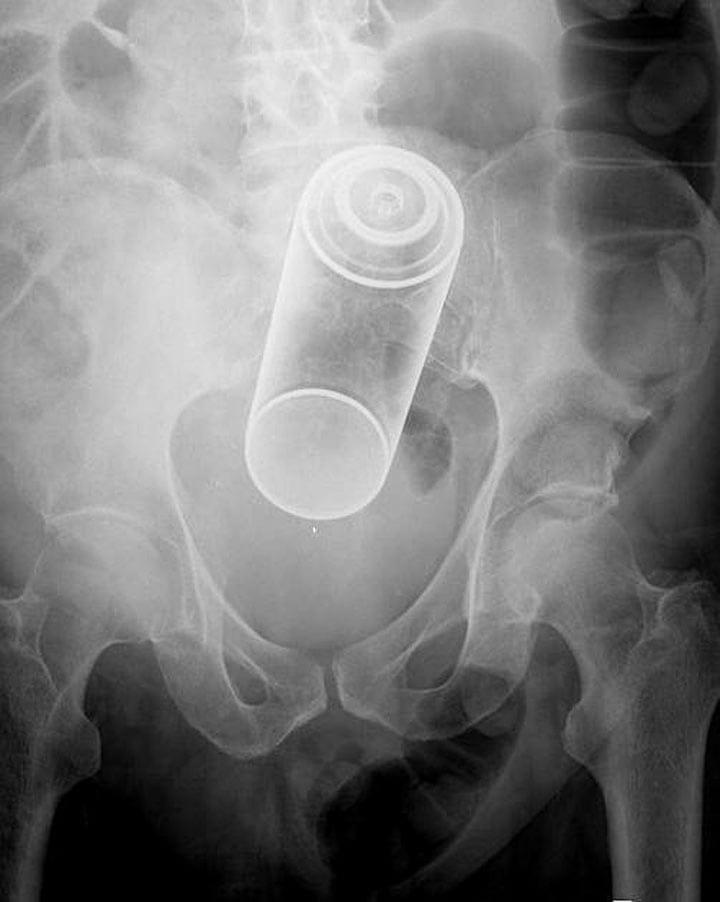

2. Оказывается, банки от аэрозолей врачи извлекают из задних проходов довольно часто